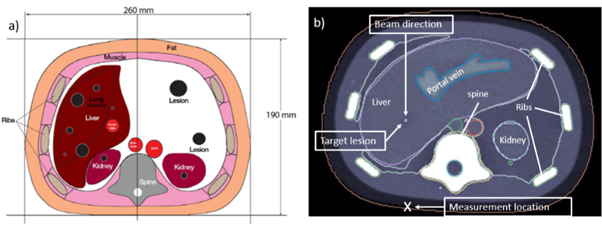

Ionoacoustic signals were measured on the surface of a CIRS triple modality 3D abdominal phantom (Model: 057A), which was irradiated with a single proton pencil beam spot of 126 MeV initial energy. A sketch from the data sheet of the CIRS phantom is shown in figure 2(a).

Figure 2. A scheme adapted from the data sheet of the abdominal CIRS phantom (a) shows the dimensions of the phantom and the internal organs. The CT image (b) additionally shows the beam direction, the target lesion and the measurement location.

Standard image High-resolution imageThe phantom mimics human anatomy in the abdominal region using organ surrogates made of different polymers. It was imaged using x-ray CT, magnetic resonance imaging (MRI) and ultrasound. Additionally it includes lesions, one of which was chosen to be irradiated in this experiment to mimic realistic patient treatment. Figure 2(b) shows a CT image of the phantom displaying the target lesion positioned in the liver, the beam direction and the position of the acoustic detector during measurements (measurement location).

2.1.2. irradiation planning

FLUKA (Battistoni et al 2007), a Monte Carlo radiation transport simulation engine, was used for the planning of the irradiation. The CT image (see figure 2(b)) of the phantom was transferred into FLUKA using the code built-in capabilities to import DICOM images (Kozłowska et al 2019). The Hounsfield units generated from the CT image were converted into the relevant material parameters such as atomic composition and mass density using the segmentation approach supported by the standard distribution of the code (Kozłowska et al 2019). Beam properties were defined starting from an analytical beam model of the CAL facility (Grevillot et al 2020), tuned to reproduce experimental depth dose measurements in water. The irradiation position was chosen such to mimic a clinical scenario (hepatic lesion in figure 2(b)) while minimising the heterogeneities in the beam and acoustic path. The proton beam energy (126 MeV) was adjusted in silico to position the Bragg peak at the lesion centre.